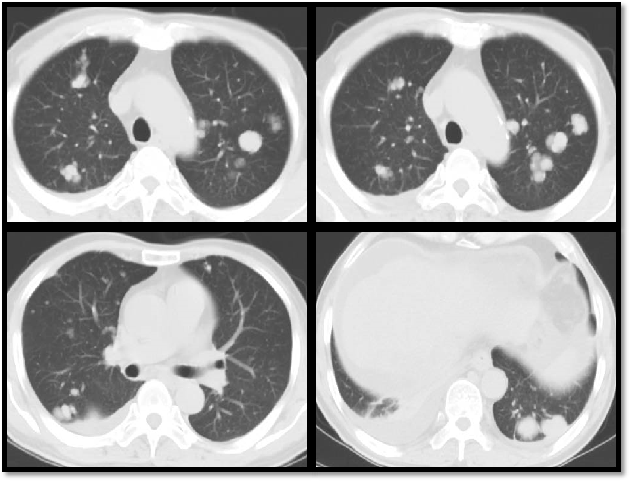

胸部CT:双肺多发转移瘤,大者大小约2.7cm×1.8cm。

胸部CT:大部分较前增大,部分缩小。

双肺转移灶较前明显增多、增大

双肺转移灶较前未见增多